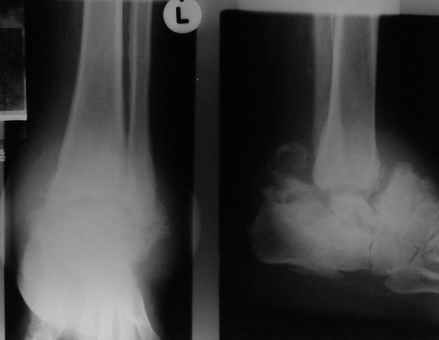

Уажаемые коллеги,представленные рентгенограмммы я показывал на нашем х-рей митинге - они были встречены с большим интересом.. Ну, ещё бы - я сам эту патологии встречал раза три за всю свою долгую жизнь:

После меня выступал с новыми находками для своей коллекции Эмануэл Лакью Тесема, хирург-ортопед из Эфиопии: Мне понравились его находки:

Кто шустрый - при какой патологии встречается так называемые "суставы Шарко"?Второе приобретение доктора Эмануэла мне понравилось своим романтическим названием: Candle bone - <кость-в-виде-оплывающей-свечи> : Просто редкая патология:

VR> Кто шустрый - при какой патологии встречается так называемые <суставы Шарко>?

Сирингомиелия,

Травма спинного мозга

Опухоль

Ленар Рашитов

Alexander Chelnokov 27 Февраль 2005, 12:17

Т.н. нейрогенная артропатия бвает при диабете, периферических нейропатиях, заболеваниях спинного мозга... Как-то довелось вести больного с таким поражением тазобедренных суставов при третичном сифилисе.